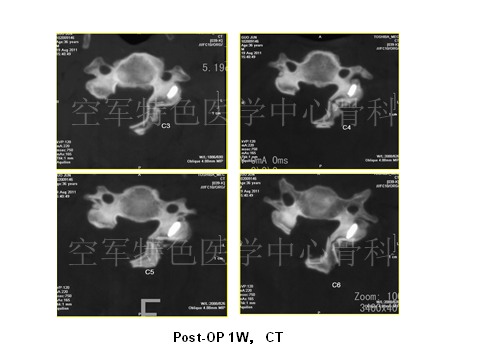

患者影像学资料如下:

最终陈医生采取的治疗方案与各位专家不谋而合,患者最终行颈后路C3-6椎管扩大成型术,术后患者自觉症状明显减轻,JOA评分:12分。术后3年随访,患者步态稳健,无明显不适。

随访影像学如下:

专家点评:对于影像学可以解释的神经压迫症状,临床还是建议积极手术治疗。该患者脑瘫诊断不明确。帕金森患者由于长期头部晃动,可能会产生脊髓刺激,临床应认真查体,仔细核对影像学,尤其应与脊髓硬化症相鉴别。脊髓硬化症手术会加重患者临床症状。同时,应积极请神经内科会诊,协助鉴别。